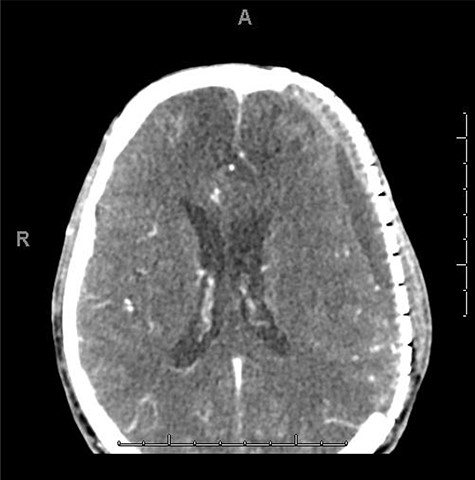

He was paralyzed, intubated and taken emergently to the OR due to nonresponsive hypovolemic shock. A right frontal ICP monitor was placed in the operating room while he was undergoing an emergency thoracotomy. Intraoperative ICP was in the 40s, and thus the patient was taken directly from the operating room to CT scan which showed enlargement of bilateral contusions, left greater than right, for which he was taken emergently to the operating room for a left hemicraniectomy (Figs 2 and 3).

CT head post thoracotomy with expansion of contusion with shift.